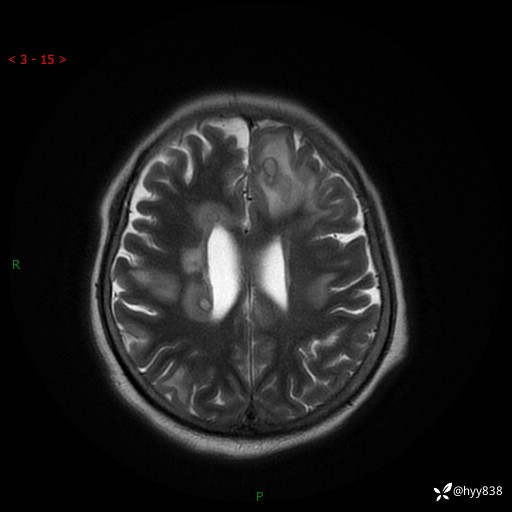

患者性别:女

患者年龄:57岁

简要病史:昏迷入院

颅脑MRI(T2WI+DWI)